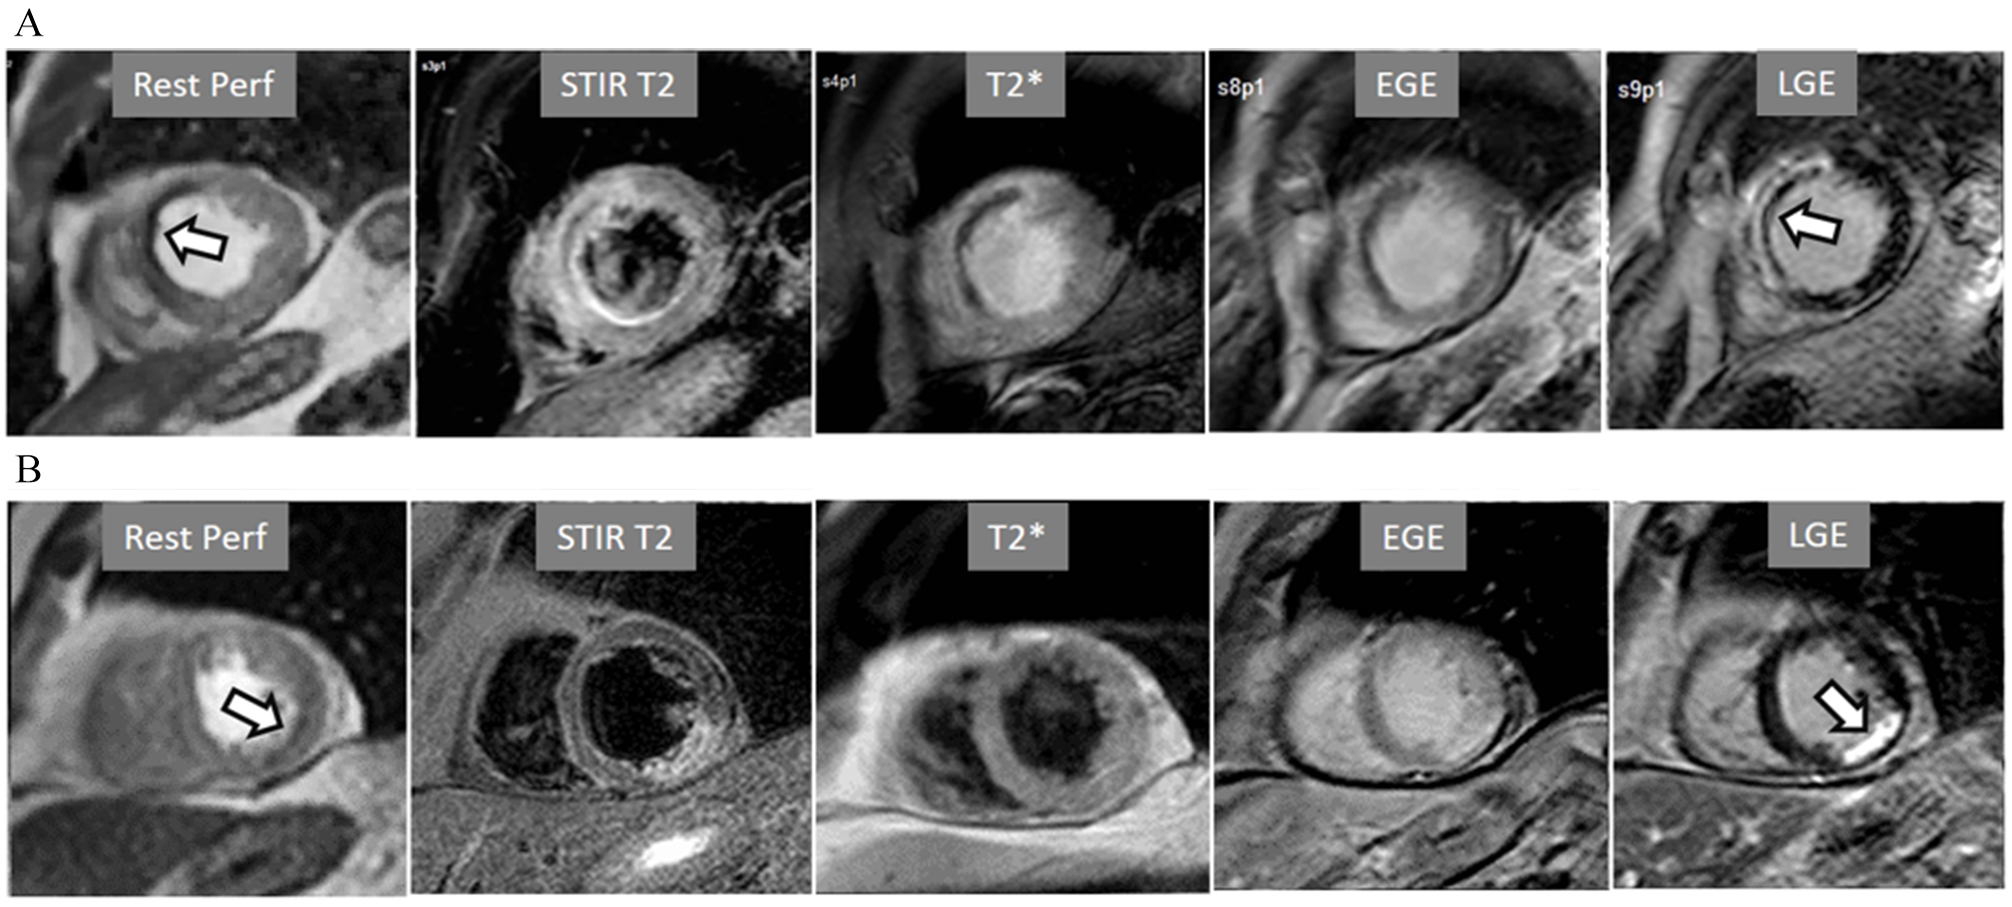

A not infrequent finding is a diffuse, annular, transient, subendocardial defect not present at rest (Fig. 9), which, in the absence of any recognizable obstructive lesion in an epicardial coronary artery, has been deemed to correspond to diffuse microvascular dysfunction (MVD) [41, 42]. CMR perfusion is sensitive to both the downstream effects of discrete epicardial stenoses and those due to disturbances of coronary microcirculation, and subendocardial hypoperfusion is on the pathophysiological basis of each one. For this reason, theoretically, a global, inducible subendocardial defect, could also be due to multivessel epicardial disease with balanced ischemia. In practice, however, this latter instance presents with extensive but heterogenous defects in terms of intensity, persistence and transmurality and, not rarely, also with perfusion defects at rest (Fig. 10A). Importantly, an accompanying induced contractile disfunction may be found in particularly impaired regions (Fig. 10B), a finding which is never seen in MVD.

Particularly important, in practice, is the issue of perfusion studies in patients with previous MI. In theory, a basal rest perfusion study should exhibit a reduced signal intensity in the infarcted area, as is the case in the acute phase of a large transmural MI (Fig. 14A). However, not infrequently, the presence and extent of a rest perfusion defect does no correlate with the actual area of necrosis in either, acute (Fig. 14B) or chronic MI (Fig. 15). Signal intensity in areas of previous MI is thus, not dependent merely on the presence of scar tissue, but some other factors lead to differences in CA concentration between MI and remote regions and, in this sense, rest perfusion CMR cannot be equated to SPECT studies, where rest defects are directly related to the presence of infarcted myocardial tissue not amenable to radiotracer uptake [45].

Fig. 14.Rest perfusion after acute myocardial infarction. (A) Frames from different sequences in a case of acute MI showing, from left to right, (1) gross transmural defect at the rest perfusion study (arrow); (2) signs of regional myocardial edema at STIR T2, with a mid-line low intensity region which proves to be due to (3) intramural hematoma at T2* sequence; (4) persistence of hypoperfusion at Early Gadolinium Enhancement (EGE); and (5) transmural anteroseptal necrosis with a subendocardial area of microvascular obstruction (arrow). (B) The same series of sequences in another patient with AMI showing (1) mild subendocardial defect at rest (arrow); (2) regional edema; (3) absence of hematoma at T2*; (4) lack of persistent defect at EGE; and, finally, (5) a transmural infero-lateral LGE (arrow) without microvascular obstruction.